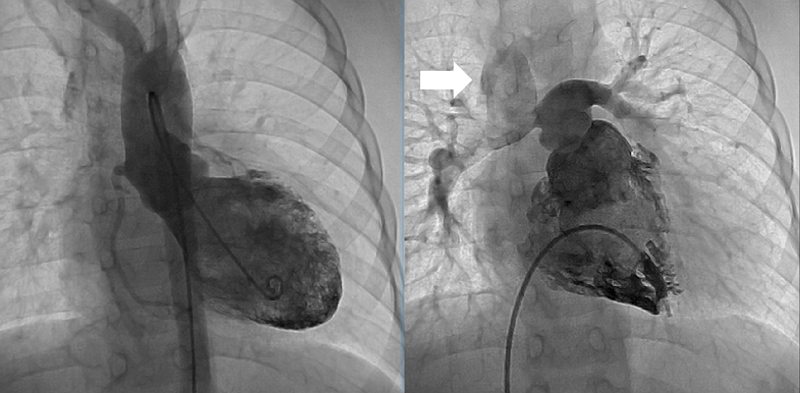

A 0-day-old boy was transferred to our hospital because of cyanosis and a heart murmur. On arrival, two-dimensional echocardiography revealed TGA, VSD, coarctation of the aorta, and a moderately hypoplastic RV with tripartite portion and a TV diameter of 7.5 mm; Z-score (the distance of the raw score value from the mean in terms of standard deviation) being −1.62. Anatomy of the coronary artery was of a usual pattern (the left anterior descending branch and the circumflex artery arising from sinus 1 and the right coronary artery from sinus 2). VSD was of a perimembranous type. RV angiography on Day 2 is shown in Fig. 1. The aortic valve diameter was 6.7 mm (Z-score: 0.14) without subaortic stenosis. Infusion of prostaglandin E1 (PGE1) was immediately initiated, but the patient developed circulatory failure due to obstruction across the ductus arteriosus. At 5 days of age, urgent bilateral pulmonary artery (PA) banding was performed; the patient was then stabilized on continuous PGE1 infusion.

Fig. 1 Right ventriculography on Day 2

Right ventricle is tripartite without obvious sub-aortic stenosis.